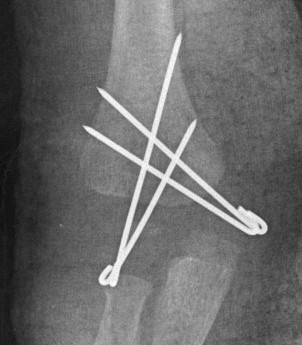

Closed reduction + percutaneous K wires

Closed reduction +/- percutaneous K wires

- 10 cases of transphyseal humeral separation in neonates

- birth trauma

- 4 closed reduction, 6 percutaneous K wire

- all healed, no deformity or functional loss

Cha et al Injury 2020

- 12 patients treated with arthrogram + K wire fixation

- normal outcomes, no AVN

May need arthrogram to visualize distal humerus epiphysis